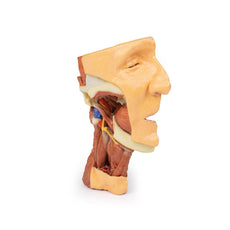

On the opposing side of the model, a superficial and deep dissection has

opened a large window into the anatomy of the lateral scalp and infratemporal

fossa. Across the scalp there is a well preserved posterior auricular nerve

and superficial temporal artery highlighted on the superficial surface of the

temporalis muscle. Anteriorly, the temporalis has been dissected to expose

the deep temporal arteries arising from across the maxillary artery.

The deep level of dissection has exposed parts of the infratemporal fossa

(through partial removal of the mandibular ramus and corpus) and dissection

of retromandibular tissues. At the inferior margin of the dissection window,

the cut edge of the retromandibular vein lies adjacent to the submandibular

gland and the ascending path of the facial artery as it cross towards to angle

of the mouth. Just superior to the cut retromandibular vein is the posterior

belly of the digastric muscle, overlying a small exposure of the deeper

internal jugular vein.

Just posterior to the retained ascending ramus of the mandible are the

external carotid artery and the occipital artery (running in parallel prior

to passing posteriorly). Tracing the external carotid artery superiorly, the

posterior auricular artery, superficial temporal artery, and maxillary artery are

all visible. The maxillary artery passes deep to the lateral pterygoid muscle

and into the infratemporal fossa, reappearing superior to the lateral pterygoid

as it passes into the pterygomaxillary fissure. Along its course, it gives rise

to the posterior deep temporal artery, the inferior alveolar artery (which is

exposed in the dissected mandibular corpus), the anterior deep temporal

artery, and the posterior superior alveolar artery. Finally, the inferior alveolar

nerve can be seen coursing within the opened mandibular corpus, and the

lingual nerve resting on the medial pterygoid. The buccinator muscle is also

retained, with the distal part of the parotid duct preserved as it enters the

muscle towards the oral mucosa